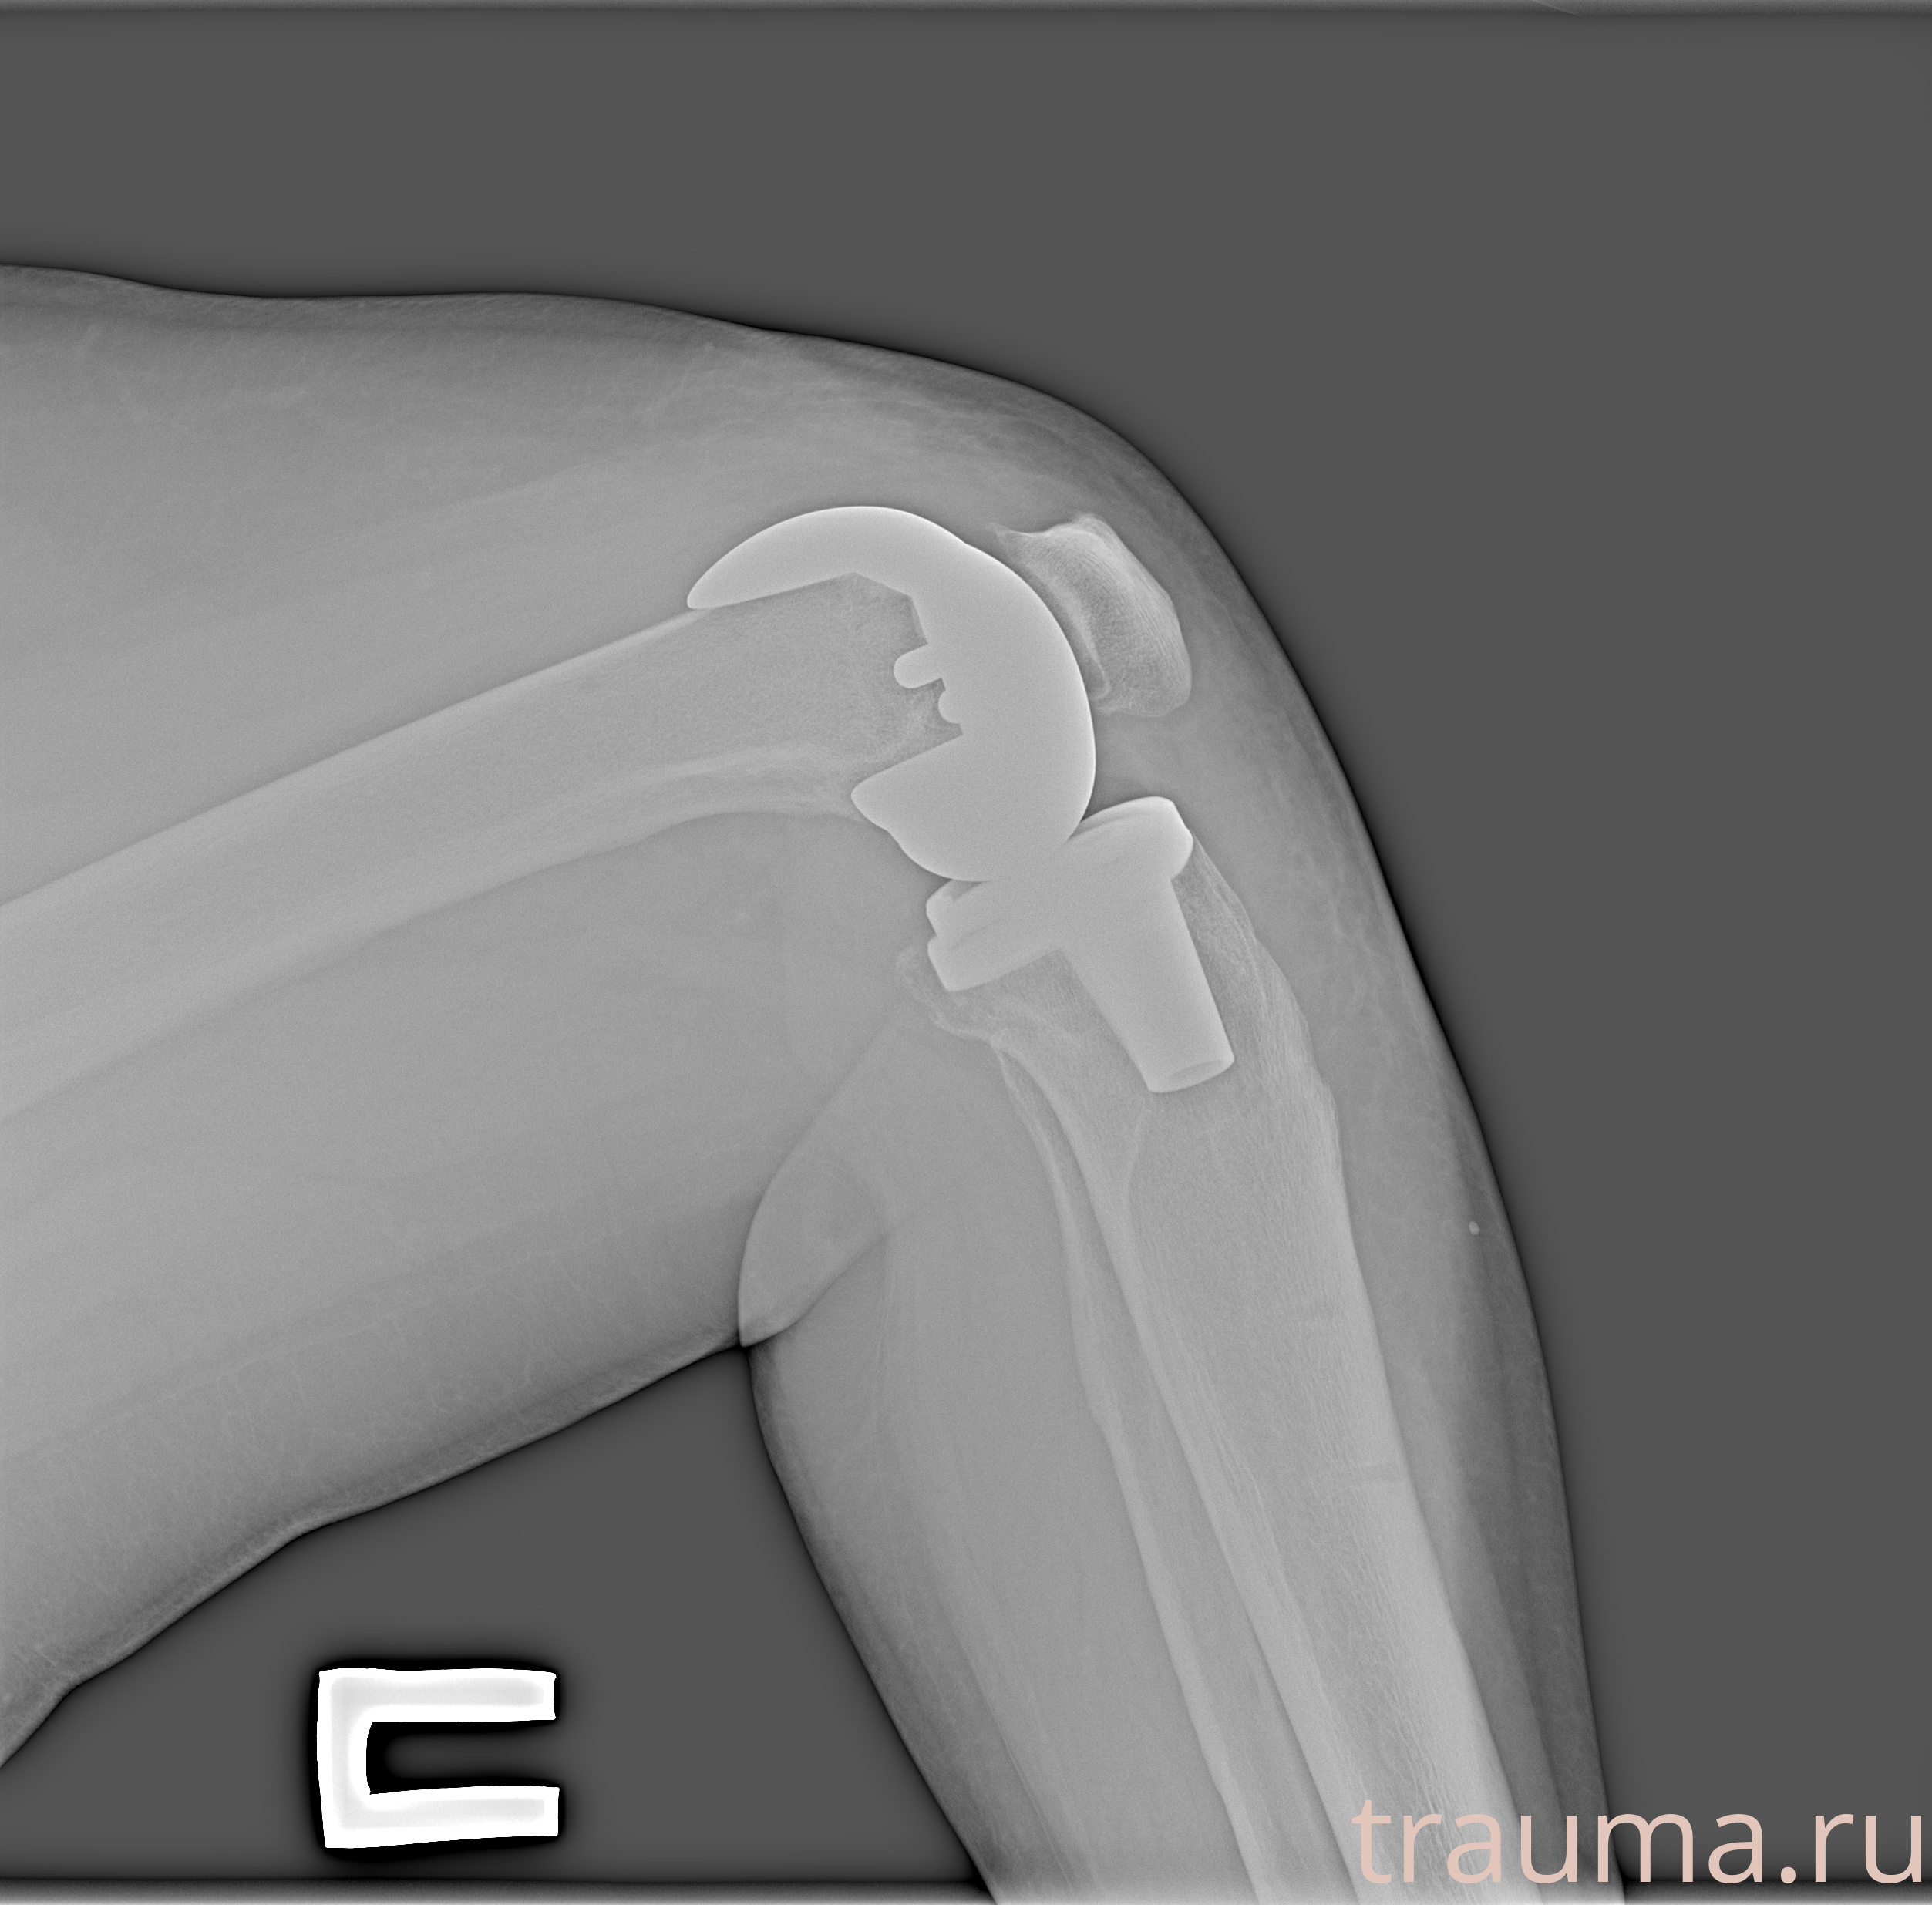

Рентгенограммы

Рентген на дому: по вашему адресу приезжает врач-рентгенолог, травматолог-ортопед с мобильным рентгеновским аппаратом, проводит диагностику травмы или заболевания, делает необходимые рентгенограммы, дает рекомендации по дальнейшему лечению. Получить качественные снимки в домашних условиях возможно благодаря уникальной методике, разработанной МосРентген Центром для института  Склифосовского